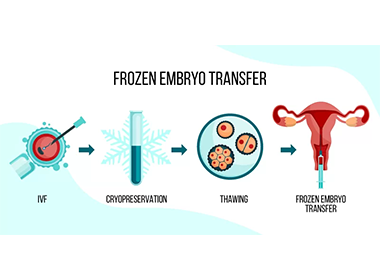

Embryo Freezing & Transfer

Storage of healthy embryos for future IVF cycles or delayed pregnancy planning.